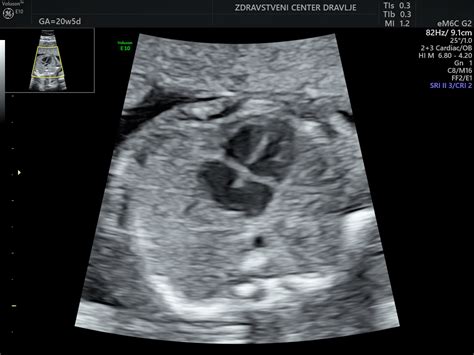

V 12. tednu nosečnosti plod meri približno 4-5 cm v dolžino in tehta okoli 10-15 gramov. Nastanek organov je v 12. tednu v največji meri zaključen. Prebavila so v 12. tednu že v trebušni votlini. Posteljica plod že lahko oskrbuje s hrano in kisikom. Glava zavzema polovico velikosti ploda. Razvijejo se očesne veke in zametki zob. Formirajo se jetra in zunanje genitalije, nastanejo nohti. Od 11. tedna dalje je možno opraviti ultrazvočno merjenje nuhalne svetline in biopsijo horionskih resic. Otrok je v 12. tednu nosečnosti zelo aktiven in s pridom uporablja prostor, ki mu je na voljo za vse vrste telovadnih vaj. Zdaj se lahko odziva tudi na dražljaje, saj so prevodni sistem srca, živčevje in možgani zdaj dovolj razviti. Če med nebrzdanim premikanjem pred svojimi majcenimi usti začuti kakršno koli stvar, se sproži njegov sesalni refleks. Izurjeno oko bi lahko z ultrazvočnim pregledom opazilo rahle premike otrokovih vek in kako popolnoma zaprti oči je še ena stvar, ki jo bo moral otrok vaditi (kasneje se bo razvilo tudi refleksno zapiranje vek). Če pritisnete na svoj trebuh, se bo otrok nenadoma odmaknil stran od trebušne stene. Spola vašega otroka še vedno ni mogoče določiti, na to boste morali še malce počakati. Pred 16. tednom vam ginekolog še ne bo mogel povedati, ali gre za deklico ali fantka.